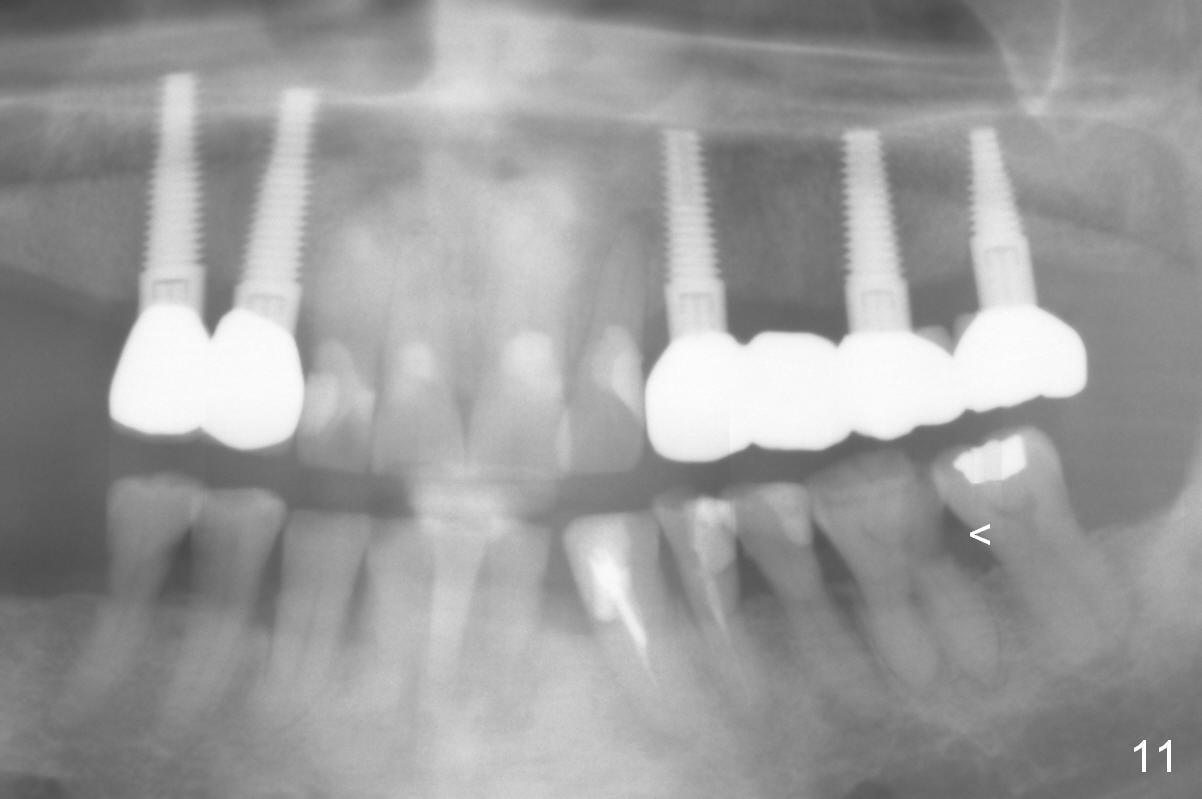

The patient keeps complaining of mastication pain on the left, 4 months post cementation (Fig.11). In fact, there is distal caries at #19 (<).